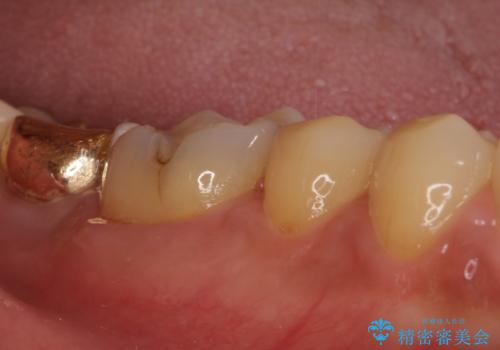

- 奥歯に装着されていたゴールドインレーが外れてしまったとのことで来院された患者様です。

外れてしまったインレーをはめたところ、インレー周辺の歯質が虫歯で失われていました。

虫歯をしっかりと取り除き、改めてゴールドインレー(PGAインレー)にて修復することとしました。